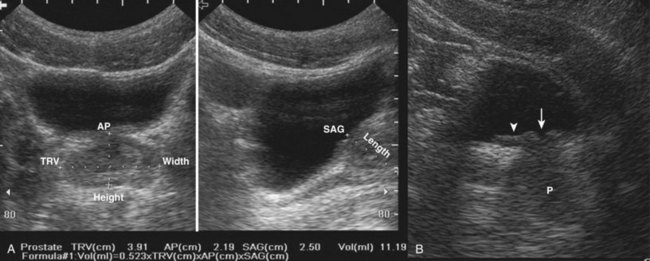

Some patients are not favorable candidates for renal ultrasonography. Obesity, intestinal gas, and physical deformity may be impediments to complete renal evaluation. Renal ultrasonography has poor sensitivity for renal masses less than 2 cm (Warshauer et al, 1988). There is a lack of specificity for renal tumor type except for angiomyolipoma. Angiomyolipoma has characteristics that are distinctive on ultrasonography (highly echoic), but some small renal cell carcinomas have been shown to be indistinguishable from angiomyolipoma by ultrasound criteria (Yamashita et al, 1992; Forman et al, 1993).

Transabdominal pelvic ultrasonography is a tremendously versatile tool for the urologist. It is a noninvasive method for evaluating the lower urinary tract and prostate in men and the bladder in women. A curved array transducer of 3.5 to 5 MHz is most commonly employed to perform transabdominal ultrasonography. In pediatric patients a higher-frequency transducer may be used. In cases where only a residual urine or bladder volume is to be determined, an automated bladder scanner is often employed.

Bladder ultrasonography is most commonly performed with the patient supine and the sonographer on the patient’s right side. The scan should be performed in a warm room, and the patient draped to provide for comfort and privacy. If necessary, a roll may be placed beneath the patient’s hips. Scanning technique depends on the circumstances and the reason for the examination but in general should be performed with a moderately filled bladder. The bladder should be scanned in a sagittal and transverse manner angling the probe into the pelvis so that the bladder can be visualized beneath the pubic bone. Although the prostate cannot be imaged with the same resolution achieved during transrectal scanning, the size and morphology of the prostate can be demonstrated. Although transabdominal scanning is the most common means of evaluating the bladder, the bladder may also be assessed via a transvaginal and transrectal approach. These approaches are useful in patients who are obese or who are not suitable candidates for transabdominal scanning.

Transabdominal pelvic ultrasonography should include evaluation of the lumen of the bladder, as well as bladder wall configuration and thickness. The presence of specific lesions such as stones or tumors should be documented. The structures immediately surrounding the bladder may also be evaluated including the distal ureters, the prostate in men, and the uterus and ovaries in women (Fig. 4–34). The emergence of urine from the ureteral orifices (ureteral jets) can be demonstrated. The clinical value of demonstrating ureteral jets has been questioned. Up to 10 minutes of continuous observation may be required to verify the absence of a ureteral jet (Fig. 4–35) (Delair and Kurzrock, 2006).